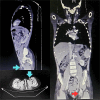

Castleman's Disease is an idiopathic rare lymphoproliferative disorder that is clinically Classified to multicentric to unicentric types. Only few cases were reported in children, with majority of them are unicentric and usually located in the mediastinum. We report a unique case of a 13-year-old boy who presented with a palpable enlarged mass in the left inguinal region without any constitutional symptoms. Surgical removal of this mass was essential to exclude worrying causes. Pathologic examination revealed proliferative changes consistent with Castleman's disease plasma cell type which is one of the rarest forms of the disease in children. To our knowledge, this case is the first reported case of Unicentric Castleman Disease (UCD) in the inguinal area. During a 12-month-period of follow-up, no additional lymph node enlargements or other symptoms were reported. In conclusion, any isolated lymph node enlargement wherever it is, especially in a child, should impose UCD as a possible differential diagnosis.